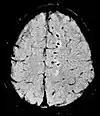

| Fluid-attenuated inversion recovery | FLAIR | Fluid suppression by setting an inversion time that nulls fluids | High signal in lacunar infarction, multiple sclerosis (MS) plaques, subarachnoid haemorrhage and meningitis (pictured).[24] | ![]() | |